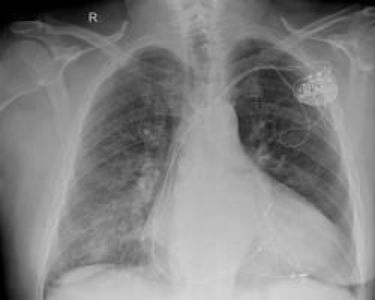

An Implantable Cardioverter Defibrillator (ICD) is a life saving device, but like any surgical procedure, it carries specific risks. In the UK, the majority of ICD implantations are performed safely with high success rates. However, patients must be aware of potential complications that can occur during the surgery, in the immediate recovery phase, or in the long term.

In this article, you will learn about the common clinical risks such as infection and bruising, technical risks like lead displacement, and the often overlooked psychological impact of living with a defibrillator. Following 2025 clinical standards, we break down these risks to help you make an informed decision about your heart health.